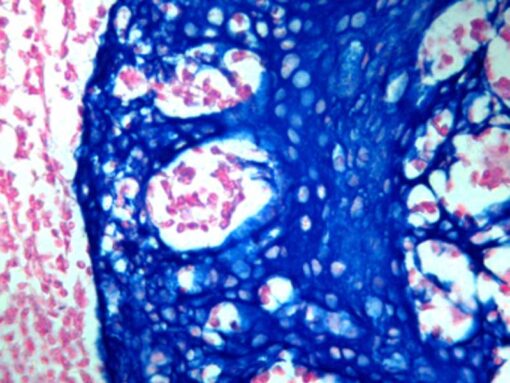

PermaBlue/HRP is a substrate-chromogen system designed to be used for either IHC or ISH when utilizing horseradish peroxidase. PermaBlue/HRP can be permanently mounted to produce a strong azure blue color that can be easily distinguished from other stains.